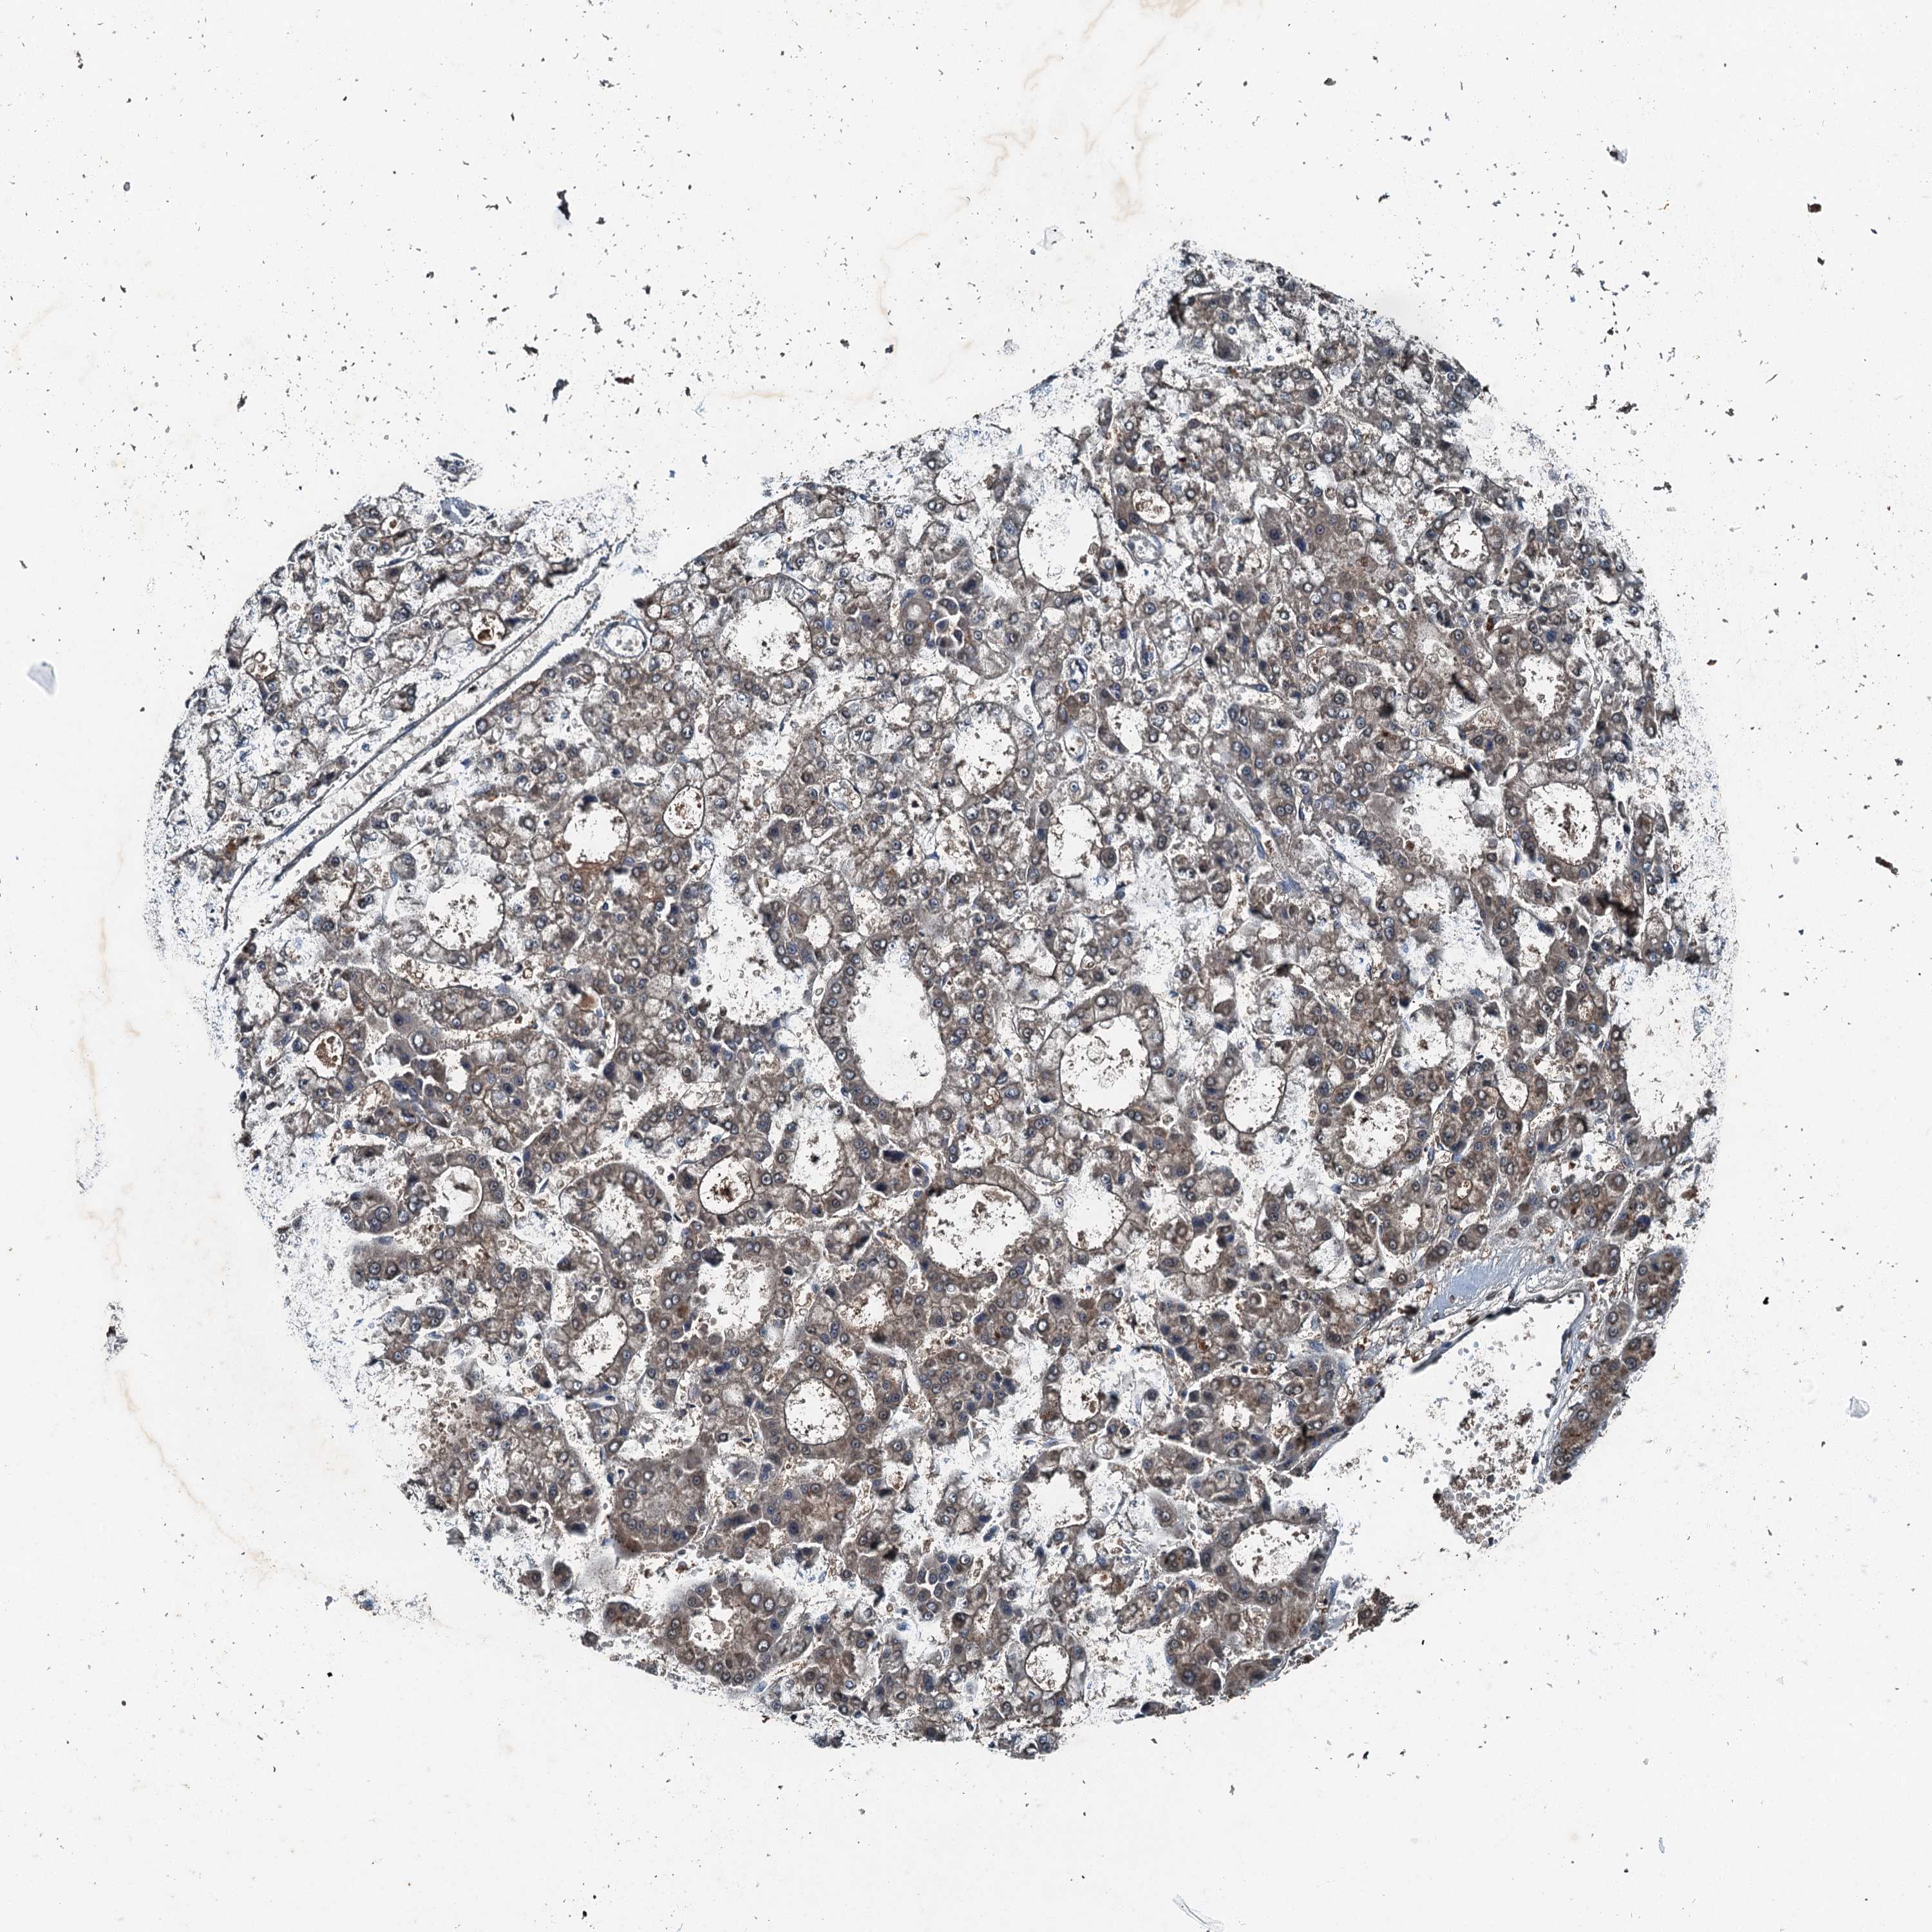

LIVER CANCER - Protein expressioni

A mouse-over function shows sample information and annotation data. Click on an image to view it in a full screen mode. Samples can be filtered based on level of antibody staining by selecting one or several of the following categories: high, medium, low and not detected. The assay and annotation is described here.

Note that samples used for immunohistochemistry by the Human Protein Atlas do not correspond to samples in the TCGA dataset.

Antibody stainingi

Antibody staining in the annotated cell types in the current human tissue is reported as not detected, low, medium, or high, based on conventional immunohistochemistry profiling in selected tissues. This score is based on the combination of the staining intensity and fraction of stained cells.

Each image is clickable and will lead to virtual microscopy that enables deeper exploration of all samples and also displays staining intensity scores, fraction scores and subcellular localization as well as patient and tissue information for each sample.

Antibody HPA039687

Antibody HPA040036

Staining

High

Medium

Low

Not detected

Intensity

Strong

Moderate

Weak

Negative

Quantity

>75%

75%-25%

<25%

None

Location

Nuclear

Cytoplasmic/membranous

Cytoplasmic/membranous,nuclear

Cholangiocarcinoma

Carcinoma, Hepatocellular, NOS